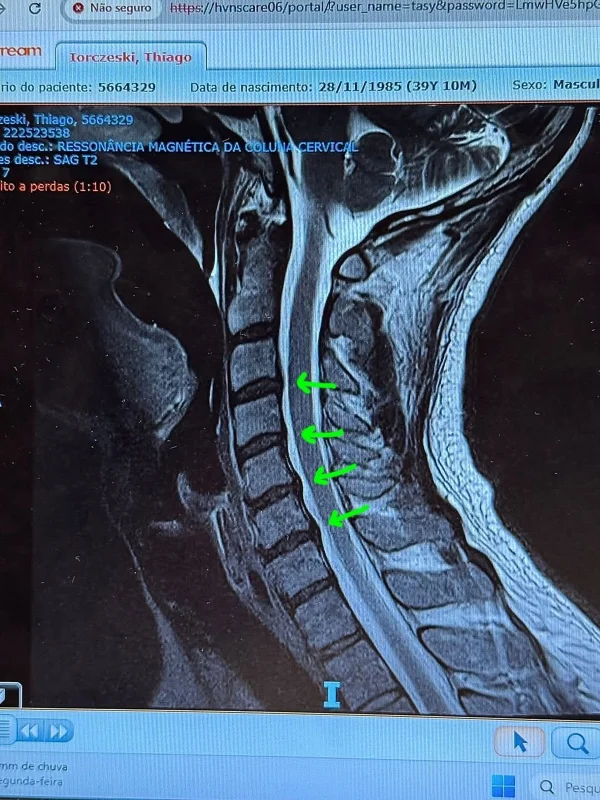

Tiago Iorc mostrou os exames que fez na unidade de saúde

Instagram/Reprodução 3 de 5

O cantor Tiago Iorc recorreu às redes sociais para acalmar os fãs após ser levado às pressas ao hospital em razão de uma crise de hérnia de disco na cervical. Nesta segunda-feira (13/10), ele compartilhou que está se sentindo melhor e com dores mais controladas. O artista passou por um procedimento de bloqueio do processo inflamatório, com a aplicação de injeções diretamente na coluna.

O cantor explicou que a crise foi resultado de anos mantendo hábitos prejudiciais à postura, como tocar violão por longos períodos e ficar com o pescoço curvado no celular. “Tive que ser internado às pressas por conta de uma crise de hérnia de disco na cervical, causada por má postura ao longo dos anos”, relatou.